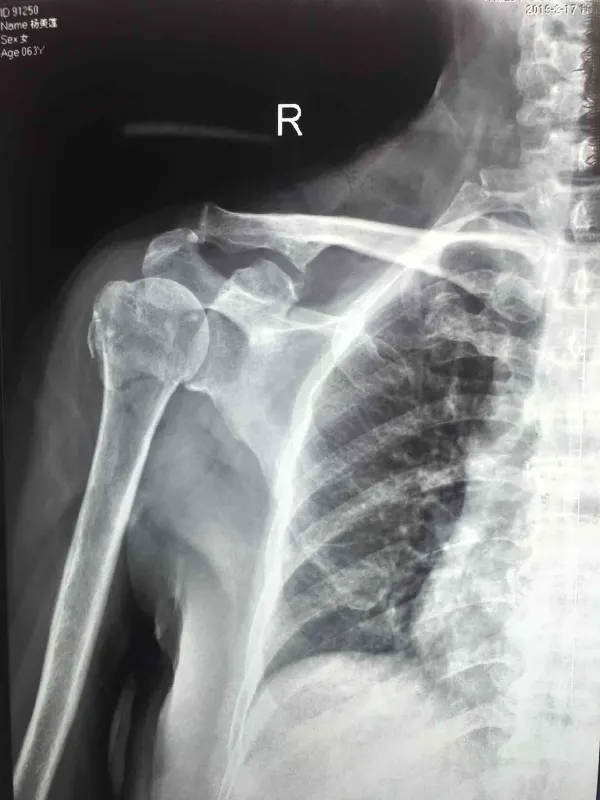

在检查时,医生通常会通过体格检查和影像学检查(如X光或CT扫描)来确认骨折的具体情况。这些检查有助于确定骨折的类型和严重程度,对于制定合适的治疗方案非常重要。

肱骨骨折是指上臂骨折,是人体最常见的骨折之一,特别是老年人群体中。主要成因包括摔倒、交通事故和其他创伤性事件。由于老年人骨骼相对脆弱,轻微的外力也可能导致骨折。

肱骨骨折的症状包括剧烈的疼痛、肿胀、畸形和无法正常移动受伤的手臂。在某些情况下,骨折部位可能会有明显的挤压痕迹或凹陷。患者可能会感觉受伤的部位非常敏感,轻轻触碰都会引发剧烈的疼痛。